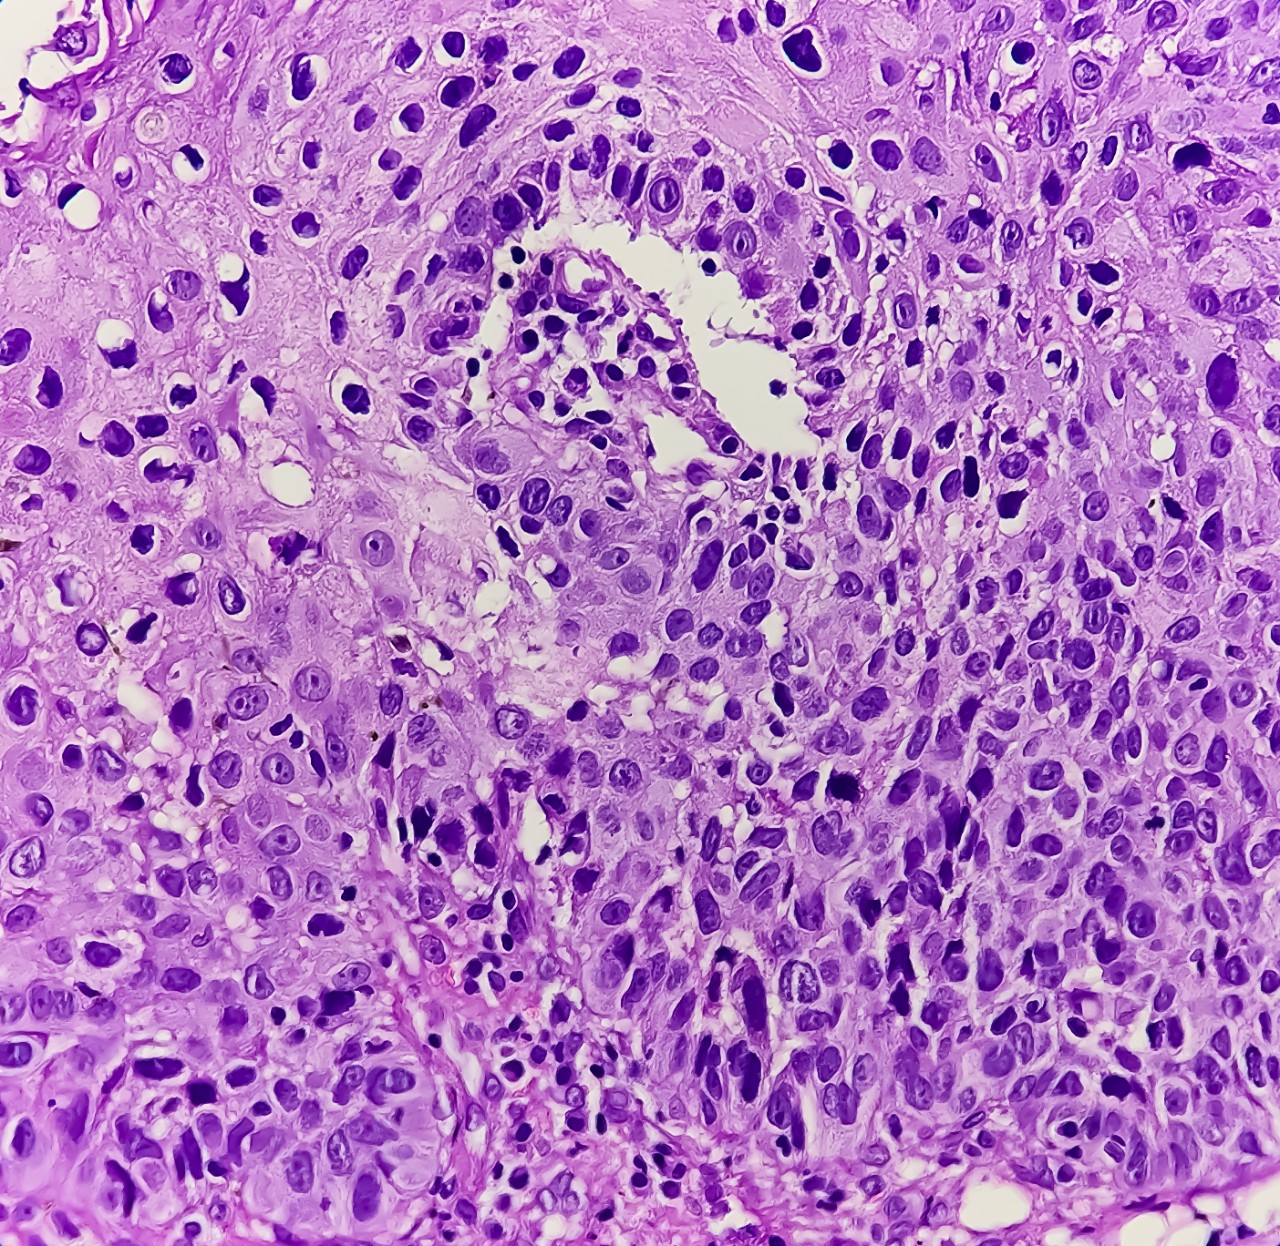

Featured photo at top of oropharyngeal cancer cells stained purple. Photo/Md Babul Hosen/iStock Photo.